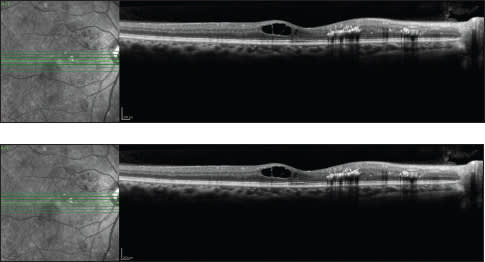

Intravitreal triamcinolone is a useful treatment modality for DME (Figure 4). However, the relatively high risk of secondary glaucoma and cataracts has made it somewhat less popular especially with the advent of anti-VEGF agents. Numerous studies have been conducted to assess the efficacy of corticosteroids to treat macular edema.

Figure 4. A patient with DME before (above) and after (below) an injection of triamcinolone.

Martidis et al. studied 16 eyes with clinically significant DME that failed to respond to at least two previous sessions of laser photocoagulation, and they observed decreases in central macular thickness by optical coherence tomography15 of 55%, 57.5% and 38%, at the one-, three- and six-month follow-up intervals, respectively, after a 0.1-mL intravitreal injection of 4 mg of triamcinolone. Intravitreal triamcinolone was effective in improving vision, reducing macular thickness, and inducing reabsorption of hard exudates in diffuse DME.7